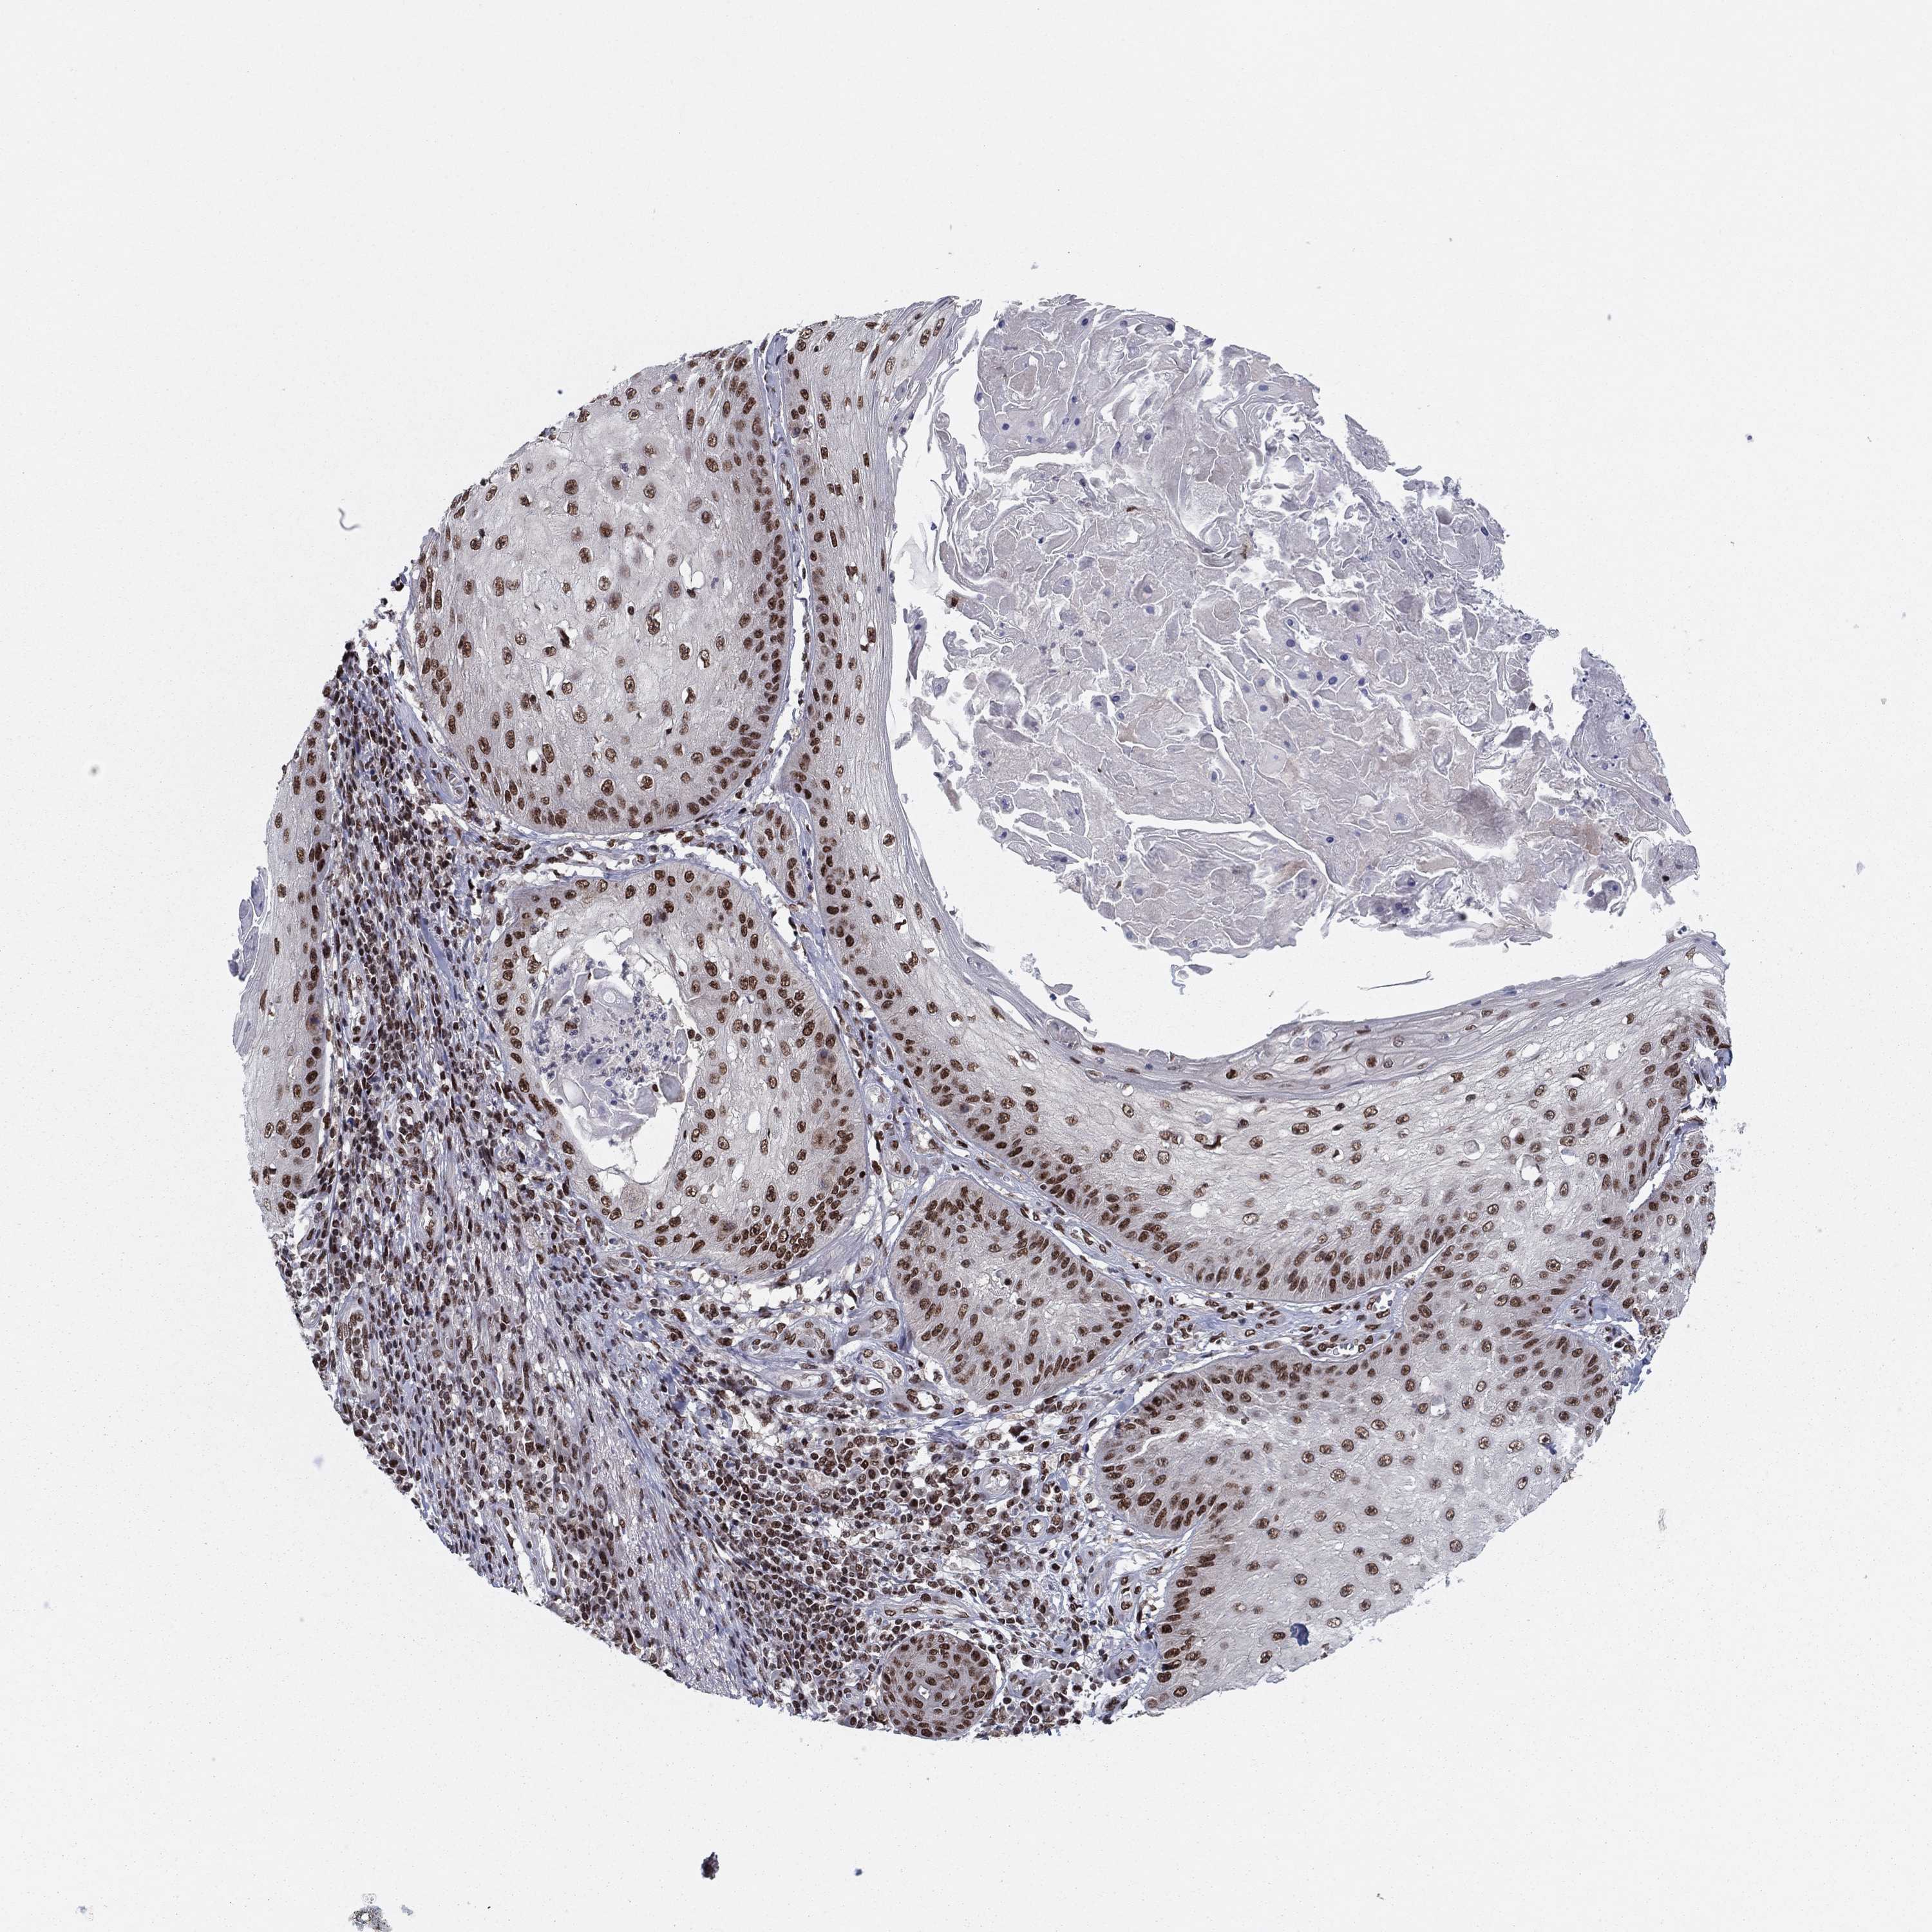

Basal cell and squamous cell cancer

SKIN CANCER - Protein expressioni

A mouse-over function shows sample information and annotation data. Click on an image to view it in a full screen mode. Samples can be filtered based on level of antibody staining by selecting one or several of the following categories: high, medium, low and not detected. The assay and annotation is described here.

Each image is clickable and will lead to virtual microscopy that enables deeper exploration of all samples and also displays staining intensity scores, fraction scores and subcellular localization as well as patient and tissue information for each sample.

Antibody HPA063665

Staining

High

Medium

Low

Not detected

Intensity

Strong

Moderate

Weak

Negative

Quantity

>75%

75%-25%

<25%

None

Location

Nuclear

Cytoplasmic/membranous

Cytoplasmic/membranous,nuclear

Basal cell carcinoma